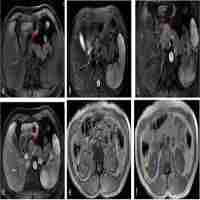

| Abstract | Background Tuberous sclerosis complex (TSC) is a rare, autosomal dominant genetic disease that arises from TSC1 or TSC2 genetic mutations. These genetic mutations can induce the development of benign tumors in any organ system with significant clinical implications in morbidity and mortality. In rare instances, patients with TSC can have malignant tumors, including renal cell carcinoma (RCC) and pancreatic neuroendocrine tumor (PNET). It is considered a hereditary renal cancer syndrome despite the low incidence of RCC in TSC patients. TSC is typically diagnosed in prenatal and pediatric patients and frequently associated with neurocognitive disorders and seizures, which are often experienced early in life. However, penetrance and expressivity of TSC mutations are highly variable. Herein, we present a case report, with associated literature, to highlight that there exist undiagnosed adult patients with less penetrant features, whose clinical presentation may contain non-classical signs and symptoms, who have pathogenic TSC mutations. Case presentation A 31-year-old female with past medical history of leiomyomas status post myomectomy presented to the emergency department for a hemorrhagic adnexal cyst. Imaging incidentally identified a renal mass suspicious for RCC. Out of concern for hereditary leiomyomatosis and renal cell carcinoma (HLRCC) syndrome, the mass was surgically removed and confirmed as RCC. Discussion with medical genetics ascertained a family history of kidney cancer and nephrectomy procedures and a patient history of ungual fibromas on the toes. Genetic testing for hereditary kidney cancer revealed a 5’UTR deletion in the TSC1 gene, leading to a diagnosis of TSC. Following the diagnosis, dermatology found benign skin findings consistent with TSC. About six months after the incidental finding of RCC, a PNET in the pancreatic body/tail was incidentally found on chest CT imaging, which was removed and determined to be a well-differentiated PNET. Later, a brain MRI revealed two small cortical tubers, one in each frontal lobe, that were asymptomatic; the patient’s history and family history did not contain seizures or learning delays. The patient presently shows no evidence of recurrence or metastatic disease, and no additional malignant tumors have been identified. Conclusions To our knowledge, this is the first report in the literature of a TSC patient without a history of neurocognitive disorders with RCC and PNET, both independently rare occurrences in TSC. The patient had a strong family history of renal disease, including RCC, and had several other clinical manifestations of TSC, including skin and brain findings. The incidental finding and surgical removal of RCC prompted the genetic evaluation and diagnosis of TSC, leading to a comparably late diagnosis for this patient. Reporting the broad spectrum of disease for TSC, including more malignant phenotypes such as the one seen in our patient, can help healthcare providers better identify patients who need genetic evaluation and additional medical care. |